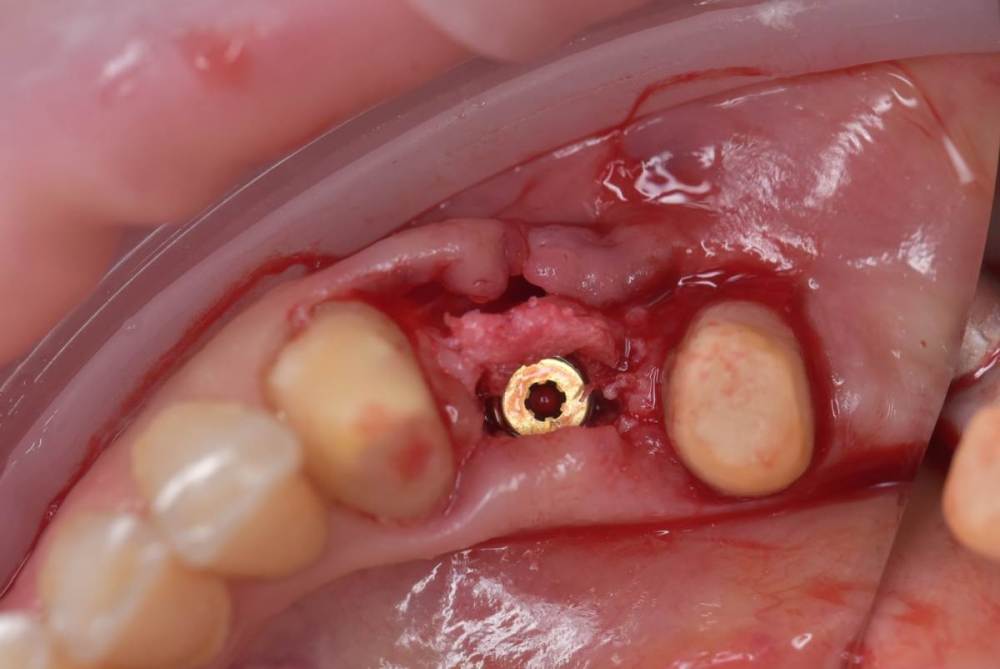

TIGER Опубликовано 10 августа, 2022 Поделиться Опубликовано 10 августа, 2022 Всем привет!Небольшой кейс с расщеплением,прошу обратить внимание на насадки,это не пилы, а остеотомы(скальпели)очень быстрое расщепление без потери тканей!Видео с операции тут 139257348_3.mp4 1 2 Ссылка на комментарий